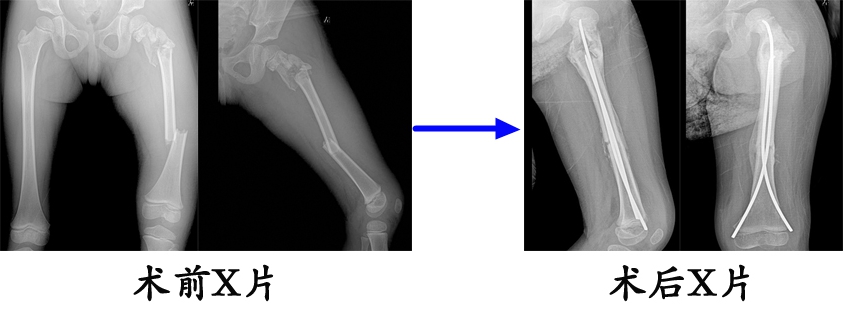

对5~11岁的股骨干骨折患儿,推荐选用弹性髓内钉治疗。

例:6岁,女,双侧股骨干骨折,在外院初次手术(髓内针直径过小,尾帽使用不当)复位不成功,来我院翻修(调整弹性髓内针直径,去除尾帽),翻修术后8个月,骨愈合良好,拆除弹性髓内针。